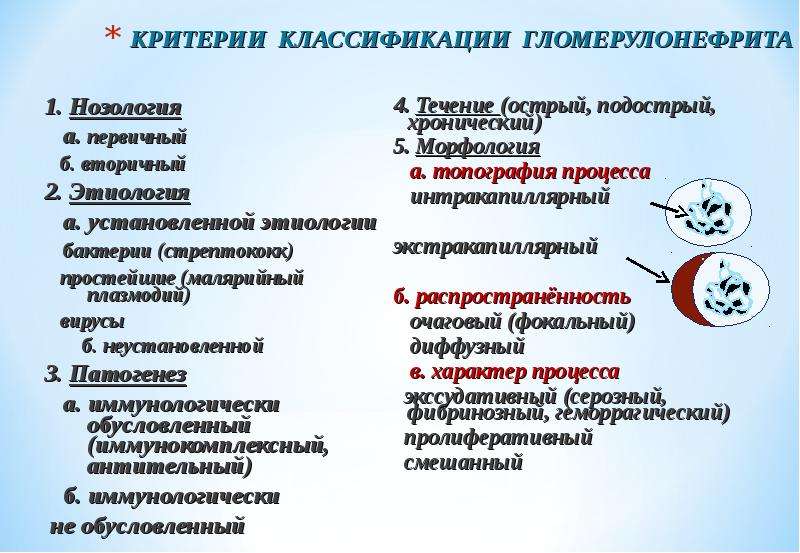

Механизм остро го диффузного гломерулонефрита